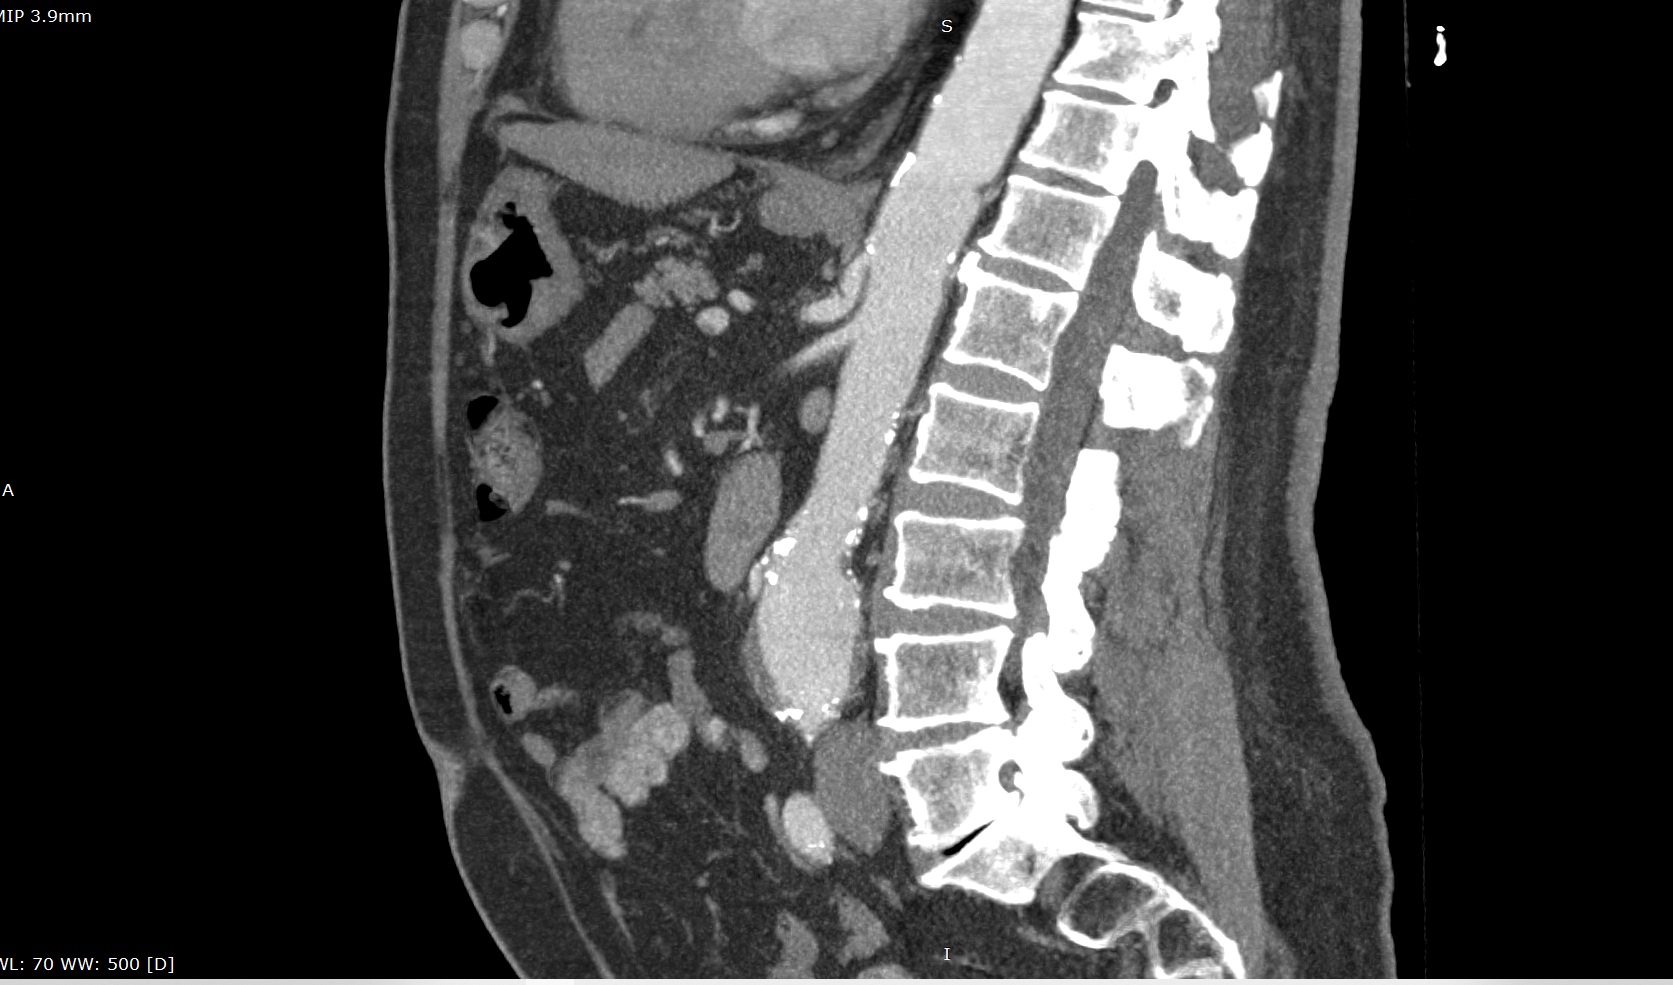

При возникновении подозрения на стеноз чревного ствола за счет экстравазальной компрессии при синдроме Данбара исследование проводится с функциональными пробами, на вдохе и на выдохе для уточнения зависимости степени сужения от фазы дыхания. При выполнении функциональных проб также возможно определить сдавление правой почечной артерии или левой почечной вены.

Мультиспиральная компьютерная томография с внутривенным болюсным контрастированием является быстрым, безопасным и неинвазивным (то есть не требующий вмешательства в организм пациента) способом диагностики патологии чревного ствола. Метод основан на использовании ионизирующего излучения и способности тканей поглощать рентгеновские лучи.

В диагностических центрах «Доступная медицина» КТ чревного ствола выполняется на современных мультиспиральных компьютерных томографах экспертного класса TOSHIBA AQUILION. Аппараты послойно сканируют исследуемую область с шагом от 0,5 мм, при этом для улучшения визуализации сосудистого русла в вену пациента вводится йодсодержащий контрастный препарат.

Контраст хорошо поглощает рентгеновские лучи, что обеспечивает высокую контрастность изображений брюшной аорты и висцеральных ветвей на снимках. С помощью инновационных цифровых приложений данные, полученные при сканировании, реконструируются в трехмерные изображения сосудистой системы. Методика обеспечивает точную и достоверную диагностику стенозов чревного ствола, при этом современные технологии, применяемые при сканировании, сводят к минимуму лучевую нагрузку на пациента.

На снимках мультиспиральной компьютерной томографии с контрастированием хорошо визуализируется брюшная часть аорты, чревный ствол, брыжеечные артерии. При этом можно выявить признаки поражения висцеральных ветвей аорты, то есть сужение просвета сосудов за счет: